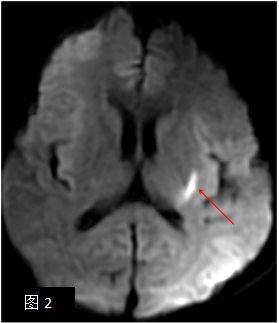

病例:急性脑血管狭窄、梗塞,男性,66岁,突发失语、左侧面瘫6小时。图1:磁共振脑血管成像(MRA)显示左侧大脑中动脉狭窄,磁共振脑功能成像-弥散成像(DWI)清晰示左侧基底节区高信号脑梗塞病灶(箭头)。

大孔径的超大空间保证患者在扫描时能够完全放松,减少躁动引起的伪影,避免患者不配合导致的检查失败。在神经功能成像方面,更重要的是不会令MR信号受到精神紧张等情绪刺激的影响,以真正反映人体机能在日常环境下的实际状态;同时,超大空间还能够有效减小噪音的声压水平,消除声音队对于人体大脑组织活动的不良干扰,获得更加准确可观的扫描数据。